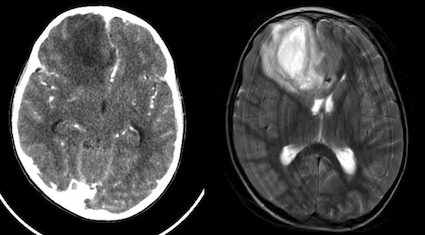

Bambino di 9 anni che viene portato in Pronto Soccorso per persistenza di febbre che dura da circa una settimana, associata a cefalea e vomito che sono comparsi nelle ultime ore. È in terapia da alcuni giorni con amoxicillina per una sinusite. Obiettivamente il bambino preoccupa, è molto pallido, risponde a tono alle domande, ma tende ad assopirsi, complessivamente il suo GCS è di 14. Allesame obiettivo neurologico il test di Lasegue è negativo e, pur non avendo un franco rigor del collo, il bambino lamenta dolore alla flessione. Eseguiamo immediatamente una dose di ceftriaxone nel dubbio di una meningite. Gli esami ematici sono subito indicativi per uninfezione con una spiccata leucocitosi neutrofila e indici di flogosi elevati. Alla luce del quadro clinico, associato a una tendenza alla bradicardia (FC 55-65 bpm), pur senza ipertensione, decidiamo di eseguire un esame neuro radiologico urgente per escludere una lesione intracranica: la TC ci mostra che il bambino ha un ascesso cerebrale frontale destro con edema limitrofo e iniziale shift della linea mediana (Figura 1). A questo punto vengono somministrati metronidazolo, desametasone e mannitolo. Il bambino viene trasferito in Neurochirurgia dove viene eseguita una RM che conferma il quadro visto in TC; viene quindi aggiunta alla terapia antibiotica la vancomicina e viene eseguito il drenaggio dellascesso. Alla luce delle difficoltà di svuotamento completo della lesione il bambino viene quindi trasferito in un Centro neurochirurgico pediatrico dove lesecuzione di un ulteriore drenaggio, associato a una variazione della terapia antibiotica con cefotaxime, cotrimossazolo e clindamicina, portano a un progressivo miglioramento del quadro.

In questo caso clinico ci troviamo di fronte a uno dei meccanismi più tipici di formazione di un ascesso cerebrale; linfezione si è infatti propagata da un focolaio di infezione contiguo (25-50% dei casi di ascesso cerebrale), una sinusite. La stessa complicanza può accadere nellotite media/mastoidite o in uninfezione odontogena. Gli altri meccanismi patogenetici sono la diffusione ematogena e linoculazione diretta (es. corpo estraneo). I sintomi (vomito, cefalea e bradicardia) sono suggestivi per unipertensione endocranica. Frequente il riscontro obiettivo di meningismo. Limaging urgente (RM se possibile, TC in alternativa) gioca un ruolo fondamentale nella diagnosi differenziale e il riscontro della tipica lesione cercinata è sempre diagnostico. Da evitare nel percorso diagnostico la puntura lombare per il rischio di erniazione cerebrale, considerando che lanalisi del liquor non aggiunge informazioni utili alla gestione o al trattamento.